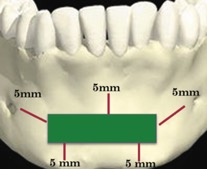

В 1992 году Misch для профилактики осложнений при получении костного блока из подбородочной области предложил правило «трёх пятёрок», при котором выделяется зона безопасности на 5 мм апикальнее от верхушек корней зубов (профилактика чувствительности зубов), на 5 мм медиальнее от ментальных отверстий (профилактика парестезии) и на 5 мм к верху от нижнего края нижней челюсти (профилактика перелома) [3] (Рис. 2).

Несмотря на данные рекомендации, питательные ветви, иннервирующие зубы, и мягкие ткани подбородочной области могут быть повреждены [5]. Это говорит о том, что необходимо знать глубину прохождения резцовой петли при планировании забора костного трансплантата в области подбородочного симфиза.

Рисунок 2. Правило трех пятерок.jpg

Рисунок 2. «Правило трёх пятеёрок»